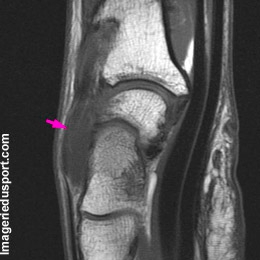

C - IRM, Coupe sagittale T1 : tendance à la bascule du semi-lunaire, à confronter à des clichés du poignet à la recherche d'un DISI.

Kyste synovial de la face dorsale du carpe.